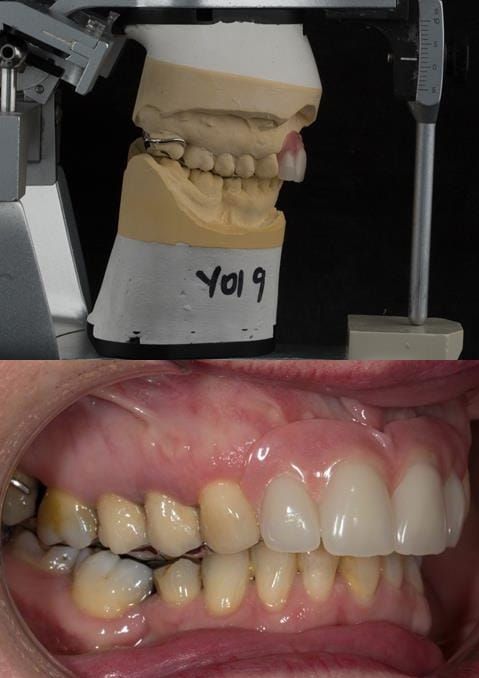

Provision of a maxillary cobalt chromium based partial denture/protective occlusal splint in a heavily restored dentition

- Extract the upper 2-2 teeth and replace with an interim acrylic based partial denture. Reline the interim denture over 9 - 12 months, replacing with a definitive cobalt chromium based partial denture. The definitive denture would ideally be designed as an occlusal protective splint to reduce the the potential for mechanical wear and breakages of the moderately/heavily restored maxillary dentition. In addition, should further upper teeth require extraction they could be added on to the denture cobalt chromium framework - therefore a new prosthesis would not be required as future teeth are lost. This option would produce an excellent aesthetic outcome. This is the option the patient chose to have.

Following consultation and second discussion appointment the patient chose to have option 3 namely, a maxillary cobalt chromium based partial denture/protective occlusal splint. The clinical situation and treatment process is shown in detail below with photographs. The patient was successfully rehabilitated with this and her quality of life considerably improved. The clinical work was provided by Finlay and the technical work by Rowan.